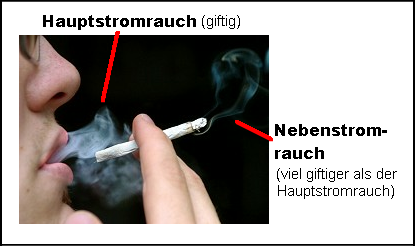

Der Raucherqualm / der Passivrauch setzt sich zusammen aus inhaliertem Rauch [Hauptstromrauch] und dem Nebenstromrauch:

-- dem Rauch, der von der rauchenden Person inhaliert und ausgeatmet wird [der Hauptstromrauch]

[2a]

-- dem Rauch, der durch das Abbrennen der Zigarette an der Zigarettenspitze entsteht,

der so genannte Nebenstromrauch bzw. Seitenstromrauch.

Rauchen verboten [1] - Man unterscheide Hauptstromrauch (gefiltert) und Nebenstromrauch (UNgefiltert) [2a] - Totenkopf [3]

Raucherin mit Hauptstromrauch. Sie begeht Körperverletzung an sich selbst und an den NichtraucherInnen.

"Der Nebenstromrauch, den auch Nichtraucher einatmen müssen, ist wegen der unvollständigen Verbrennung vier Mal so toxisch wie der Hauptstromrauch, den der Raucher inhaliert. Auch dies sei der Industrie schon durch Studien aus den 60er Jahren bekannt, deren Ergebnisse sie unterdrückt habe."

Die Schadstoffe aus dem Nebenstromrauch / Seitenstromrauch gelangen ungefiltert in die Luft. Die Schadstoffkonzentration im Nebenstromrauch / Seitenstromrauch ist deswegen z.T. massiv höher als im inhalierten Rauch, der vom Raucher wieder ausgeatmet wird.

Vergleich Hauptstromrauch - Nebenstromrauch

Der Nebensromrauch, der die Passivraucher so sehr schädigt, enthält dabei wesentlich höhere Mengen an PAK, Azaarenen und Aminen als der Hauptstromrauch. Untersuchungen ergaben einen 10fach höheren Anteil dieser Verbindungen.